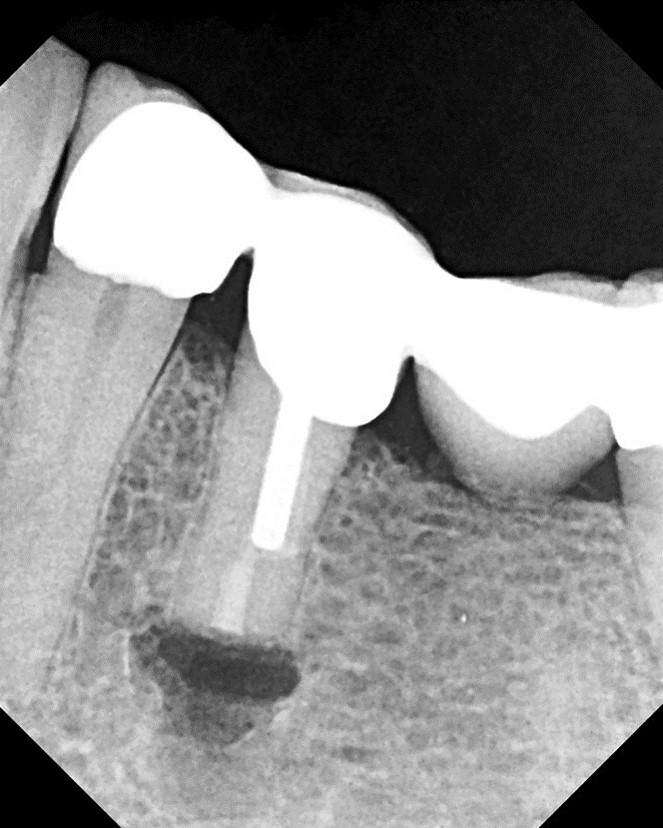

4. Several cases, including endodontic retreatments, have healed in as little as 3-4 months (Figure 19 and Figure 20).

Fig 19. Preoperative 3D CBCT image before retreatment of tooth No. 14.

Figure 19

Fig 20. 3D CBCT image of tooth No. 14 at 4 months after single visit retreatment using multisonic ultracleaning technology.

Figure 20